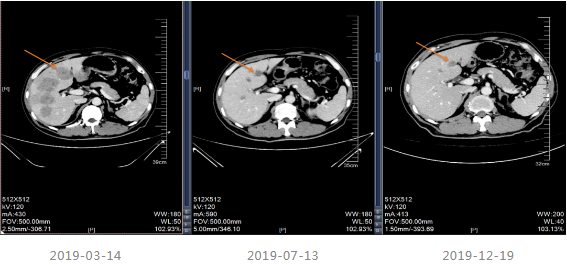

2019-03-14行上腹部增强CT,显示肝内散在的多发圆形稍低密度灶,大小不等,边界欠清晰,较大者直径约5.2cm,其内密度不均,增强扫描病灶周边有强化,内部有更低密度区液化坏死区,考虑转移瘤;胆囊多发结石;双肾多发结石,直径小于0.2cm;扫描范围内结肠肝区管壁增厚,管腔狭窄,增强扫描可见明显强化。

△2019-03-14上腹部(包括肝、胆、脾、胰范围内)平扫+增强

治疗期间于2019-07-13及2019-12-19进行疗效评估,疗效评价PR,建议患者切除原发灶,患者拒绝。CEA、CA199降至正常范围。